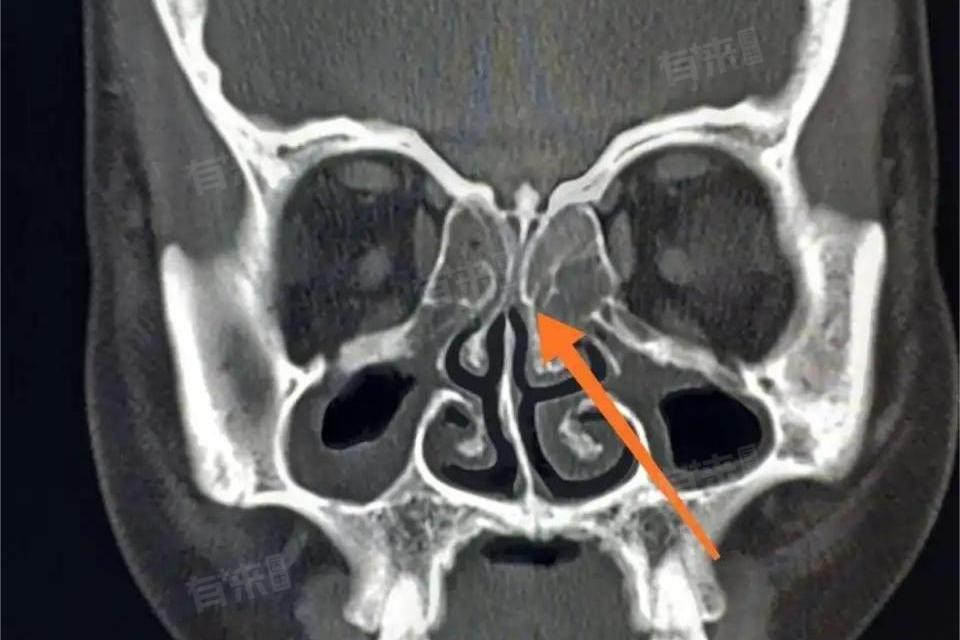

筛窦黏膜增厚是在影像学检查,如鼻窦CT或MRI中观察到的一种表现。筛窦位于鼻腔两侧、眼眶之间,是人体鼻窦的重要组成部分。正常情况下,筛窦黏膜很薄,在影像中仅显示为极细的一层结构。当出现筛窦黏膜增厚时,表明筛窦内部发生了病变。

- 炎症是导致筛窦黏膜增厚的常见因素。上呼吸道感染引发的急性炎症,可蔓延至筛窦,使筛窦黏膜充血、水肿,进而出现增厚。慢性鼻炎、鼻窦炎长期存在,炎症持续刺激筛窦黏膜,促使其不断增生,也会造成黏膜增厚。过敏反应同样会累及筛窦黏膜,当过敏原进入鼻腔,免疫系统启动,筛窦黏膜因过敏炎症而充血、水肿,导致增厚。此外,鼻腔内的解剖结构异常,如鼻中隔偏曲,影响筛窦的正常通气与引流,也可能引发筛窦黏膜增厚。